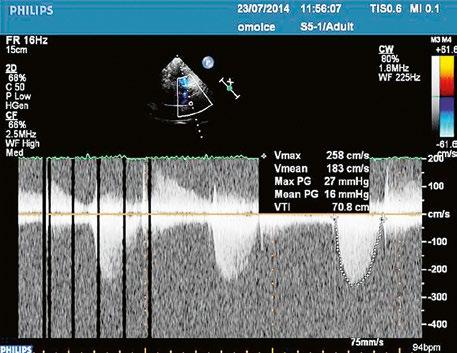

Malé restriktivní defekty komorového septa (Rogerova choroba) nevedou ke vzniku plicní hypertenze ani k srdečnímu selhání. Mají typickou vysokorychlostní dopplerovskou křivku (Obr. 45.35), odpovídající vysokém gradientu mezi levou a pravou komorou v systole a poslechovému nálezu hlučného systolického šelestu.

Obr. 45.35 CW záznam vysokorychlostního dopple rovského toku z levé do pravé komory malým restriktivním defektem komorového septa. Vysoký gradient na komorovém defektu vylučuje vysoký tlak v pravé komoře při plicní hypertenzi nebo při těžké stenóze plicnice.